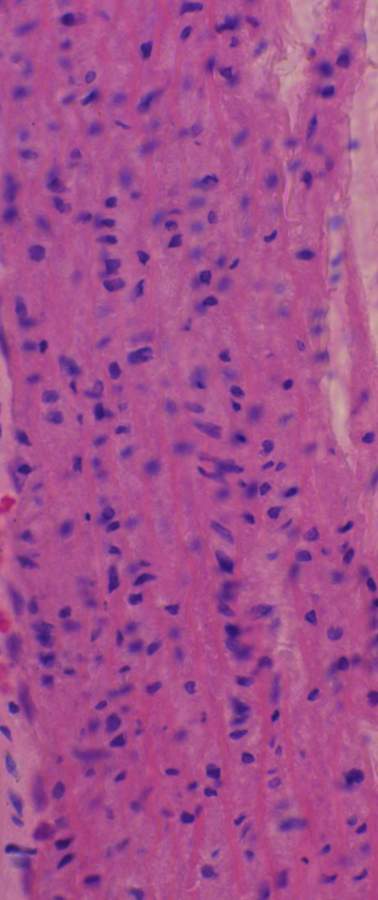

SD大鼠-心-HE染色,求高手帮我分析一下 已有1人参与